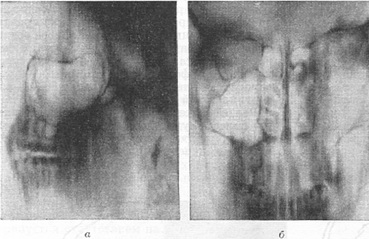

Іноді дуже важливо отримати на бічному знімку черепа (на якому тіні його симетричних половин накладаються один на одного) роздільне зображення анатомічних елементів правої і лівої сторін. В таких випадках проводиться додаткове пошарове рентгенологічне дослідження (див. Томографія). Цей метод показаний при дослідженні черепних ям, коли передбачається одностороннє збільшення турецького сідла (рис. 7, а), при поглибленні і деструкції верхньої стінки однією з орбіт (рис. 8, в), для визначення стану стінок придаткових пазух носа одного боку (рис. 9, а і б). При дослідженні повітроносних пазух користуються також спеціальними проекціями черепа як при звичайних знімках, так і при томографії (рис. 8, а-в).

Рис. 8. Рентгенологічне дослідження передньої черепної ями. Пухлина правої орбіти: а - рентгенограма черепа в правій бічній проекції, деструкція верхньої стінки правої орбіти не визначається; б - томограма черепа в лівій бічній проекції (на здоровій стороні), цілість верхньої стінки не порушена; в - томограма черепа в правій бічній проекції (на хворій стороні), глибина шару обох томограм однакова (5 см). Повна відсутність лінійної тіні верхньої стінки правої орбіти (деструкція).

Рис. 9. Пошарове дослідження черепа. Пухлина лівої половини порожнини носа: а - томограма черепа в лівій бічній проекції; видно контури всіх стінок одній (лівій) нормальної гайморової пазухи; б - томограма черепа в передній прямій проекції, глибина шару 4 див. Ліва половина порожнини носа розширена, ліві носові раковини погано диференціюються (деструкція), ліва гайморова пазуха затемнена (пухлина).